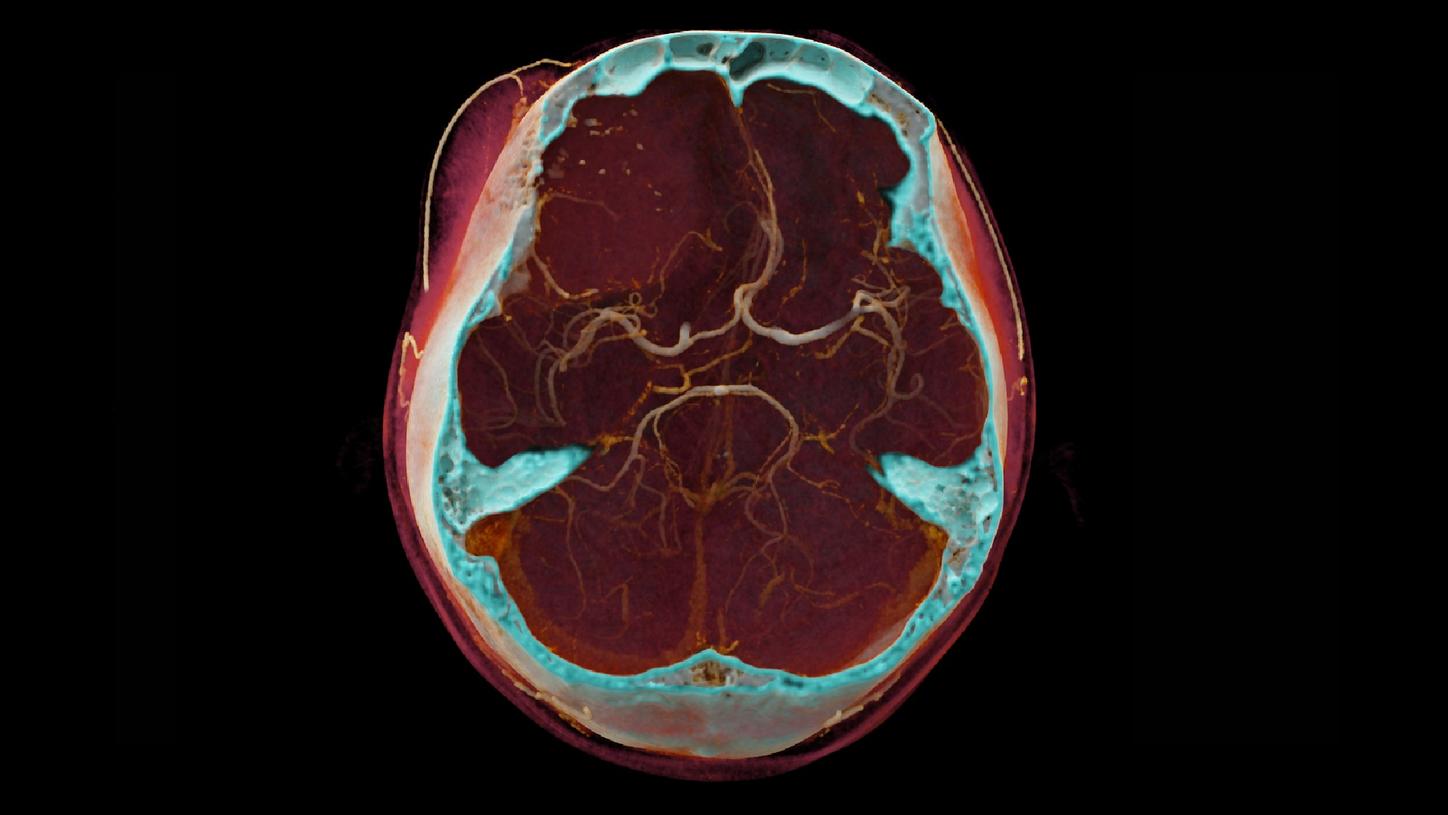

Computed Tomography is moving beyond its traditional diagnostic role to become a key player in early disease detection and therapy planning. This

expansion means an even broader patient cohort and resilient productivity demands. You need a reliable partner with products, services, and the

infrastructure to support new business models and prioritize environmental sustainability and robustness. Computed Tomography at Siemens Healthineers,

with its legacy of listening for almost 50 years, is innovating ahead of these developments, even before potentials become needs.